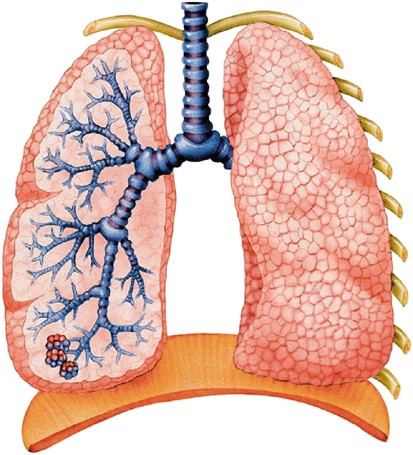

Лёгкие человека: Учебные картинки для детей